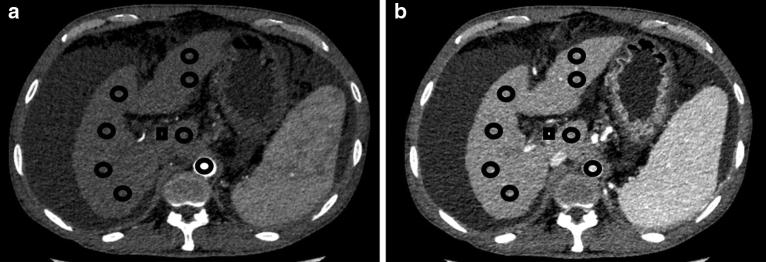

To compare changes in spectral CT iodine densities of hepatic parenchyma and vessels before and after transjugular intrahepatic portosystemic shunt (TIPS) in hepatitis B virus (HBV)-related liver cirrhosis. Twenty-five patients with HBV-related liver cirrhosis who received TIPS for gastroesophageal varices bleeding were recruited. Each patient underwent three phases contrast CT before and after TIPS within 4 weeks, with the raw data reconstructed at 1.25-mm-thick slices. Iodine density (in milligrams per milliliter) was measured on iodine-based material decomposition image. Multiple regions of interest (ROIs) in liver parenchyma, aorta and portal vein were selected from three slices of images. Portal vein trunk was set as the central one, and mean liver parenchymal iodine densities from arterial phase (AP), venous phase (VP) and equilibrium phase (EP) were recorded. Quantitative indices of iodine density (ID), including normalized ID in liver parenchyma for arterial phase (NIDLAP), ID of liver parenchyma for venous phase (IDLVP), ID of portal vein in venous phase (IDPVP) and liver arterial iodine density fraction (AIF), were measured and compared before and after TIPS. Based on Child-Pugh stage, 4, 12 and 9 patients were classified as grade A, B, and C, respectively. Liver volume was comparable before and after TIPS (1110.5 ± 287.4 vs. 1092.0 ± 276.3, P = 0.28). After TIPS, ID was decreased in aorta (146.0 ± 34.5 vs. 120.9 ± 30.7, P < 0.01) whereas increased in liver parenchyma at arterial phase, as demonstrated by IDAP (9.3 ± 3.1 vs. 13.4 ± 4.4 mg/mL) and AIF (0.40 ± 0.11 vs. 0.58 ± 0.11, P < 0.01). For venous or equilibrium phase, quantitative indices remained stable (23.1 ± 4.5 vs. 23.0 ± 5.3, 19.8 ± 4.1 vs. 19.4 ± 4.6) mg/mL (Ps > 0.05). For portal vein, ID and NID were increased after TIPS (23.1 ± 11.7 vs. 36.5 ± 13.0, 16.4 ± 8.5 vs. 31.8 ± 12.8) (P < 0.01). No positive correlation between iodine density and preoperative Child-Pugh score was observed. Based on iodine density measurement, spectral CT as a noninvasive imaging modality may assess hepatic parenchyma and vascular blood flow changes before and after TIPS in HBV-related liver cirrhosis.Clinical registration number: ChiCTR- DDC-16009986.